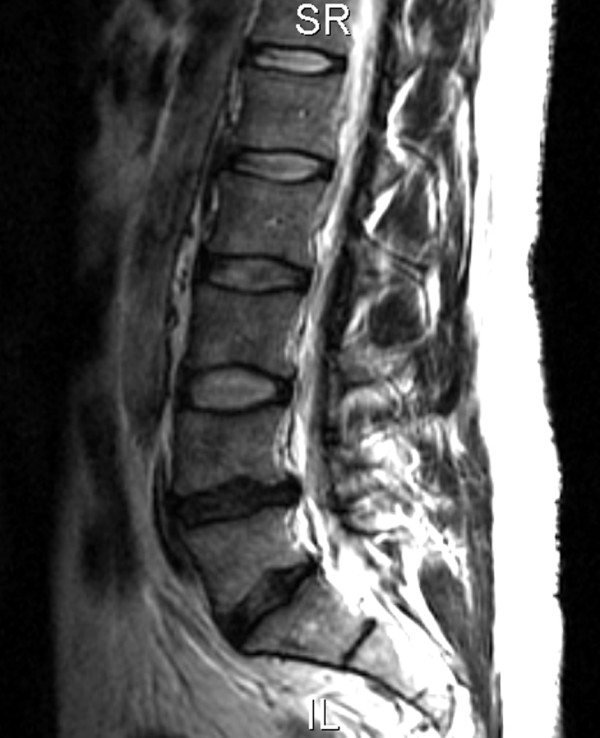

Figure 1

Plain film radiographs showed mild narrowing of the L4–L5 intervertebral disc space and mild sclerotic changes of the posterior elements of L5. MRI demonstrated a loss of normal height and signal involving the L4–L5 disc and a broad-based left paracentral disc bulge contacting the thecal sac and causing mild narrowing of the central spinal canal at the L4–L5 level with mild to moderate left neural foraminal narrowing and L5 nerve root contact (Figure 1). A lesser degree of L5–S1 disc degeneration was present with a broad-based disc bulge causing no central canal or neural foraminal narrowing.